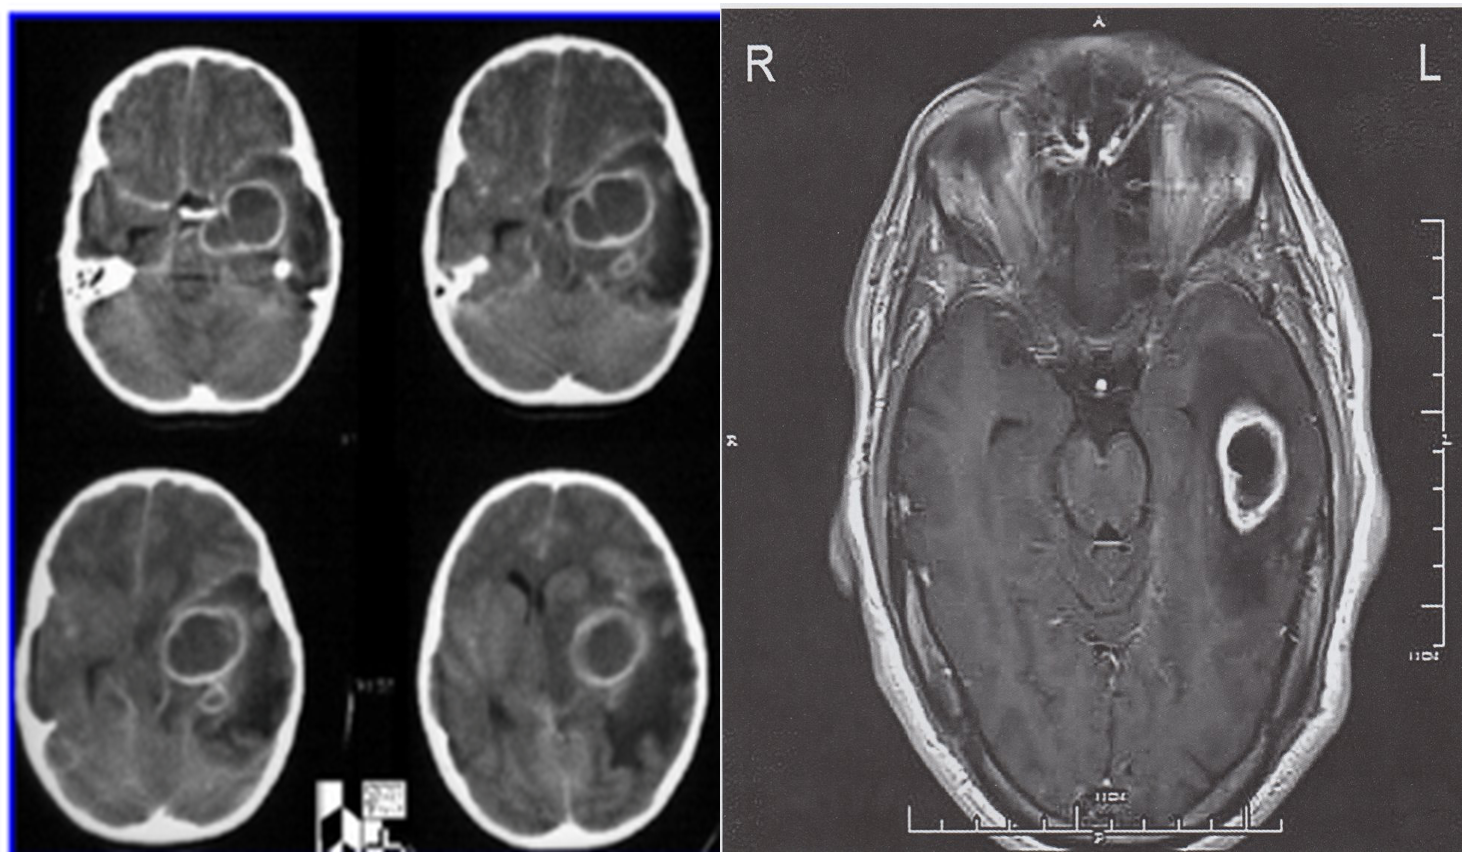

Ring-enhancing lesion left temporal lobe

Cranial MRI (with contrast, axial view)

An oval lesion can be seen in the left temporal lobe, with ring-like contrast enhancement and central necrosis . The perifocal edema that is visible corresponds to the lesion. Differential diagnoses include an abscess, glioblastoma, and metastasis.

Diagnosis: abscess following advanced otitis media